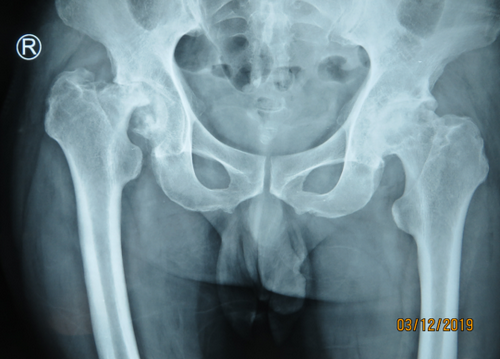

正好关节组长邱东新医生坐诊,他给王师傅做了详细检查,髋关节已经不能自如活动了,而且右腿比左腿短了有4厘米,因为长期腿短,腰也跟着变形,已经出现侧弯了;X片上看到右侧股骨头已经没有了,非常严重,必须做髋关节置换手术,而且手术难度也明显增大。

患者因为股骨头坏死长期拖延,致使右腿短了4厘米,走路一瘸一拐,腰也变形了。

“如果出现股骨头坏死了,不要拖太久才过来治,后果可能很严重。像这个病人就是因为股骨头坏死,早就发现了,但是拖得时间太长,他整个股骨头都已经磨没有了,一条腿短得特别厉害,短了有四公分,手术的难度大大增加,因为手术中需要把腿再拉长四公分出来。如果超过了五公分,就不敢一期把腿拉长了,会出现神经损伤的。而且因为腿需要拉长,手术创伤也比较大,所以说,如果股骨头有坏死的话,别等到非常非常晚期再做,不仅手术创伤会非常大,恢复期也相应的会特别长。”邱东新医生提醒。